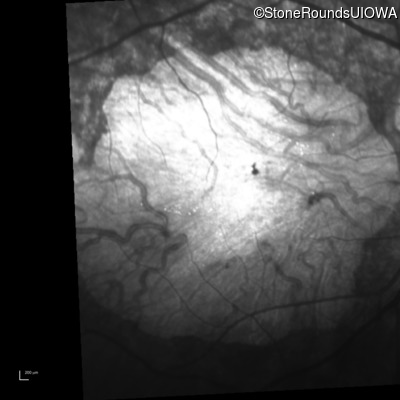

Infrared Fundus Photograph - Left - 10/200 -3 sc

Exemplar